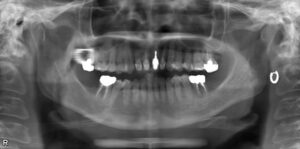

上下5本欠損症例

BEFORE AFTER 62歳女性/上下5本欠損/インプラント埋込手術 【治療内容】 欠損歯が多いため、お食事が取りに…